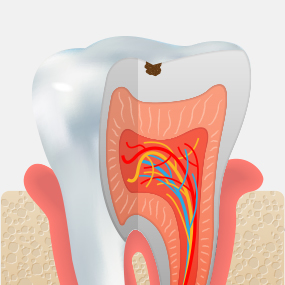

Stages of Dental Caries and Treatment Methods

• Dentin Caries

Decay has progressed into the dentin beneath the enamel, and sensitivity may occur when eating hot or cold foods.

Inlay

• Pulpitis

Inflammation has progressed to the dental pulp, causing severe pain that may become difficult to tolerate.

Root Canal Treatment + Crown

• Pulp Necrosis

The tissue inside the tooth has become necrotic, and bone around the root is gradually lost due to infection.

Extraction + Implant